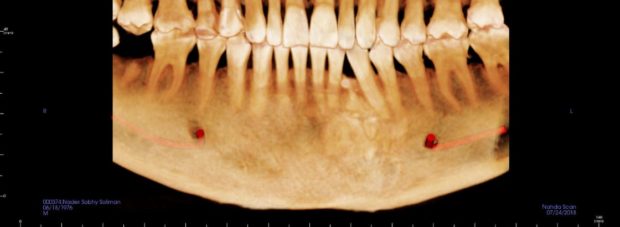

اكتب تجربتي الشخصية هذه شهادة حق لهذا الإنسان الأستاذ الدكتور محمد المفتي استاذ جراحة اللثة و الفم و الوجة و الفكين. دكتور محمد المفتي هو نجل عالم جليل في جراحة الوجة و الفكين الأستاذ الدكتور شريف المفتي رحمة الله عليه و اعرفه معرفة شخصية و تقابلت معه بالعيادة في المهندسين بعام ٢٠١١ و ٢٠١٢ للكشف و في الحقيقة ذهبت في ٢٠١٨ شهر يناير الماضي للكشف في نفس العيادة و لكن علمت أن توفاة الله و موجود نجلة الأستاذ الدكتور محمد المفتي استاذ بجامعة عين شمس كلية طب الأسنان و فعلا كما قالوا في الامثال ” اللي خلف مامتش” قام دكتور محمد المفتي بفحص الفم واللسان و الشفاة و الأسنان و اللثة و الفكين للتأكد من عدم وجود أي شيء غير طبيعي و انا في الحقيقة بطبعي قلوق جدا . طلب منى اشعة بانوراما عادية علي الفكين و عملتها و تم عرضها علية فعاد و طلب مقطعية للتأكد من شيء موجود تحت الناب الايسر بالفك السفلي و بالفعل عملت المقطعية و تم عرضها علية و قالي هنتابعها هى حاجة عندك من سنين طويلة يمكن اكتر من ٢٠ سنة و موجودة في اشعات البانوراما القديمة اللي كنت بتعرضها علي دكتور شريف المفتي في ٢٠١١ و ٢٠١٢ رحمة الله علية هى اسمها compound odontoma و حاجة حميدة تماما و لا خوف منها و ممكن تعيش بيها لكن هنتابع حجمها بالمقطعية كل ٦ شهور و متقلقش منها .

المهم انا ابتديت اقلق و لفيت علي دكاترة مشهورة بالقاهرة بدون ذكر اسماء منهم من جعل حياتي جحيم حتي اليوم الوسواس القهرى يطاردني من كلامهم الذي حتي الان لا يفارق أذني منهم من قال لي عملية و فورا و لازم نستأصل الورم بسرعة و احتمال كمان نستأصل معاة جزء من الفك و تحليل العينة لإثبات كونة خبيث ام حميد. ! قلبي هيقف من الكلام و لا اكل ولا نوم و لا راحة ..! الغريب أن انا اتصلت علي دكتور محمد المفتي و قولتلة بدون ذكر الاسم ان فية دكتور قالي كذا علي الفور دكتور المفتي ضحك و قالي انت روحت عند الجزار! قولتلة مين ! قالى فولان و قالك كمان العملية هتتكلف كذا قولتلة صح حصل ! قالي انت لو عاوز تعملها اعملهالك و مش عاوز منك فلوس لكن انا بقولك دى مجموعة اسنان زيادة مطلعوش من وانت صغير لان اسنانك كانت كاملة حوالي ٦ او ٧ تحت الناب و حجمهم تقريبا ٢ سم و قولنا نتابعها فقط بالمقطعية مش واثق فيا شوف حد تاني و بالفعل قالي روح لدكتور فولان انسان محترم و اعرض علية الموضوع عشان ترتاح و ابقي بلغني قالك اية بالفعل روحت و تم عرض كل شيء علية قالي نصا تنساها تماما و تعيش حياتك انا هاخد منك فلوس و اشتغل بس حرام عليا مش محتاجها و كتبلي تقرير قولتلة طيب نتابعها كل ٣ شهور و لا ٦ شهور عشان ممكن تكبر او تتحول لخبيث قالي مش بتتحول مستحيل و لا تعمل مقطعية تاني و لو عملت بعد سنتين هتلاقي الحجم دا زى ما هو دى حاجة بتكبر ببطىء شديد جدا علي مدار سنين طويلة جدا . المهم رجعت للدكتور محمد المفتي قالي ها صدقت !! بس معلش هنعمل مقطعية بعد ٦ شهور قولتلة حاضر . من حرق دمى دخلت علي الواتس للدكتور اللي قالي لازم نستأصل بسرعة و قولتلة شوف كدا الإشاعات القديمة دى من ٢٠١١ و ٢٠١٢ قالي مش فاضي كلمني الصبح قولتلة انت دكتور عار علي مهنة الطب و عار علي الإنسانية و تاني يوم اتصلت بية و غير كلامة تماما و قالي مافيهاش حاجة و حاجة حميدة ممكن تتعايش معاها بس الخوف ليحصل اي خبطة في الفك ينكسر! رجعت للدكتور المفتي قولتلة الكلام دا قالي ولا هيتكسر و لا هيحصلة اي حاجة . و كان دايما يقولي ربنا حلو اوى انت انسان قريب من الكنيسة عندكم آباء رائعين و انت بتعرف البابا نفسة و كل الأساقفة الناس دى هتخلى عندك قوة روحية عالية . و عاوز اقول ان دكتور محمد المفتي بيرفض حتي ياخد مني الكشف و اي وقت ارن علية اشكيلة من اي حاجة او تطور يقولي متنزلش مخصوص القاهرة صور اللي تاعبك صور كويسة واضحة سواء لسان لثة اسنان و ابعتلي علي الواتس و ارجع اتصل بية يرد عليا و يطمني و يقولي كلة طبيعي. انت نفسيتك تعبانة يا باشمهندس حد ضايقك الفترة دى ! حصل حاجة مضيقاك و افضفض معاة … بصراحة الراجل دا اتحملني فوق الوصف و اخيرا عدى ٦ شهور و ذهبت اعمل تنظيف الأسنان بعدها تعبت جدا و ندمت اني نظفت اللثة التهبت و مازالت تعباني بعد التنظيف .. قولت اعمل اشعة بانوراما مع نفسي كدا اطمن علي المشكلة.. لقيت الحجم شكلو متغير عن اللي فاتو بتوع ٢٠١٨ و ٢٠١١ و ٢٠١٢ بعتها لدكتور محمد المفتي واتس و اتصلت علية .. قالي مالك مال صوتك مخنوق ! قولتلة انا ملاحظ تغيير قالي نعمل مقطعية قولتلة فين قالي مضطر تنزل القاهرة كدا و بعدين سكت شوية و هو عارف ظروف ماما تعبانة بجلطة و مفيش غيري معاها.. قالي اسمع قولتلة نعم قالي جامعة النهضة بني سويف قريبة منك؟ قولتلة طبعا قالي انا هكون موجود هناك غدا بكلية طب الأسنان تعالي و هنعمل مقطعية عندنا و بالفعل روحت قالي اسمع البانوراما دى بايظة و مش هيطلع اي تغير قولتلو لاء يا دكتور انا ملاحظ الاشعة و الفرق قالي ماشي يا فندم بينا المقطعية!

و من قلقي كل شوية اتصل علية و الراجل يرد و يشرح و يشرح و انا منتظر المقطعية لحد ما عملت المقطعية من يومين و تركت ال cd للدكتور محمد المفتي لان وجدتة في اجتماع مع رئيس جامعة النهضة بني سويف و اول مرة كنت اعرف من الناس اللي في الجامعة ان دكتور محمد المفتي يبقي وكيل كلية طب الأسنان جامعة النهضة بني سويف و ايضا استاذ دكتور بجامعة عين شمس القاهرة مكان تواجدة.

و بعد عرض ال cd قومت بالاتصال علية قالي مافيش اي تغير يا نادر زى ماهي و مافيش حاجة تخوفني.